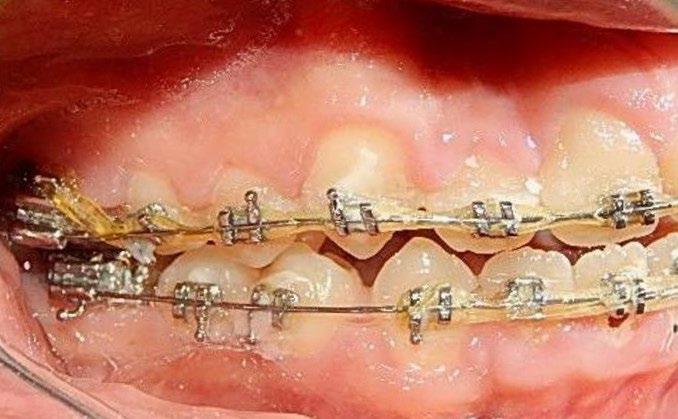

En los estudios intraorales, las fotografías iniciales muestran clase I canina y molar bilateral, mordida anterior abierta, apiñamiento leve superior e inferior, y líneas medias dentales

desviadas. En las Figuras 4, 5 y 6 se observa la forma de las arcadas superior e inferior.

Figura 4. Lateral derecha.

Figura 5. Intraoral de frente e izquierda.

Figura 6. Oclusal superior e inferior de inicio.